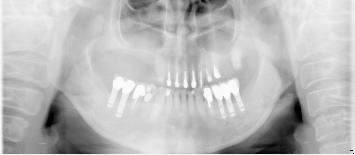

50代女性

歯がこのままではダメだと思い、一念発起された50代女性の方です。

もちろん治療期間が長期にかかることも、治療費が高額になることも、外科的な手術が何度か必要であることなど、

インプラント治療と咬み合わせ治療のほぼ全てを大名歯科ホームページで予め知っていただいた上で決心され来院されたそうです。

インプラント治療は顎骨が乏しかったため、増骨手術も併用しなければならない難症例でした。

治療期間中は残存歯数が少ない上に、丈夫でないため生活に不自由な点がでました。

さらに咬み合わせが安定しにくい症例のため、プラスチック仮歯がよく壊れたり、外れたりして、修理に来院していただくなど大変な苦労とご迷惑をおかけしました。

審美性(見た目)は十分回復できたと思っており、患者さんも大変満足されています。

食事は当然のことかもしれませんが、よく咬めるようになったそうです。

咬み合わせ治療は非常に難しいため、これで十分かどうか分かりませんが現在もこのまま定期的なメインテナンス中です。

術前

↓↓↓↓

術後